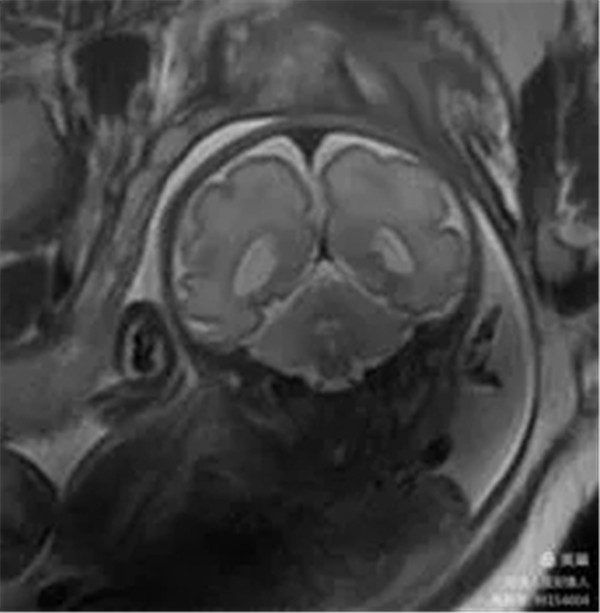

2、胎儿颅脑磁共振成像

病例12:评估胎儿颅脑发育情况。

图7,冠状位T2WI-显示胎儿颅脑